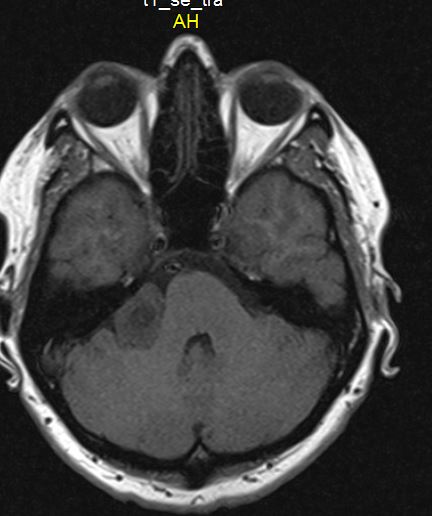

Более точно установить диагноз «невринома слухового нерва» помогает рентгенография и методы нейровизуализации. На ранних стадиях при малых размерах невриномы (до 1 см) она, как правило, не визуализируется при помощи КТ головного мозга. Поэтому проводят рентгенографию черепа с прицельным снимком височной кости. В подтверждение диагноза вестибулярной шванномы свидетельствует расширение внутреннего слухового прохода. Поскольку невриномы хорошо поглощают контраст, возможно использование КТ с контрастированием. При этом визуализируется образование с четкими гладкими контурами.

МРТ головного мозга в случае невриномы выявляет на Т1-взвешенных снимках гипо- или изоинтенсивное, а на Т2-взвешенных - гиперинтенсивное образование. Для опухолей размером 3 и более см характерна гетерогенность сигнала, связанная с наличием в них кистозных участков. Возможна визуализация деформации ствола мозга и мозжечка. При проведении контрастной МР-томографии в 70% наблюдается гетерогенное накопление контраста.